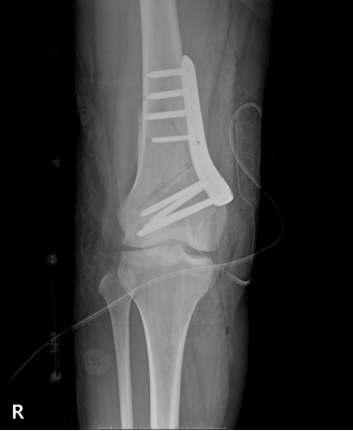

▶수술 전_X-ray

입원 후 정밀 측정을 통해 확인한 결과,

LDFA: 82도

목표 교정 각도: 기계적 축이 O도(일자다리)가 되도록 설정

일반적으로 5도 이상의 변형이 동반된 경우, 연골 이식술 단독으로는 예후가 좋지 않은 경우가 많습니다.

따라서 저는 DFO를 병행하는 것이 최선이라고 판단했고, 수술은 계획대로 진행했습니다.

수술 중 확인한 연골 이식 부위(OATS site)는 안정적으로 고정되었고, 정렬 교정도 목표에 맞게 진행할 수 있었습니다.

▶수술 후_X-ray